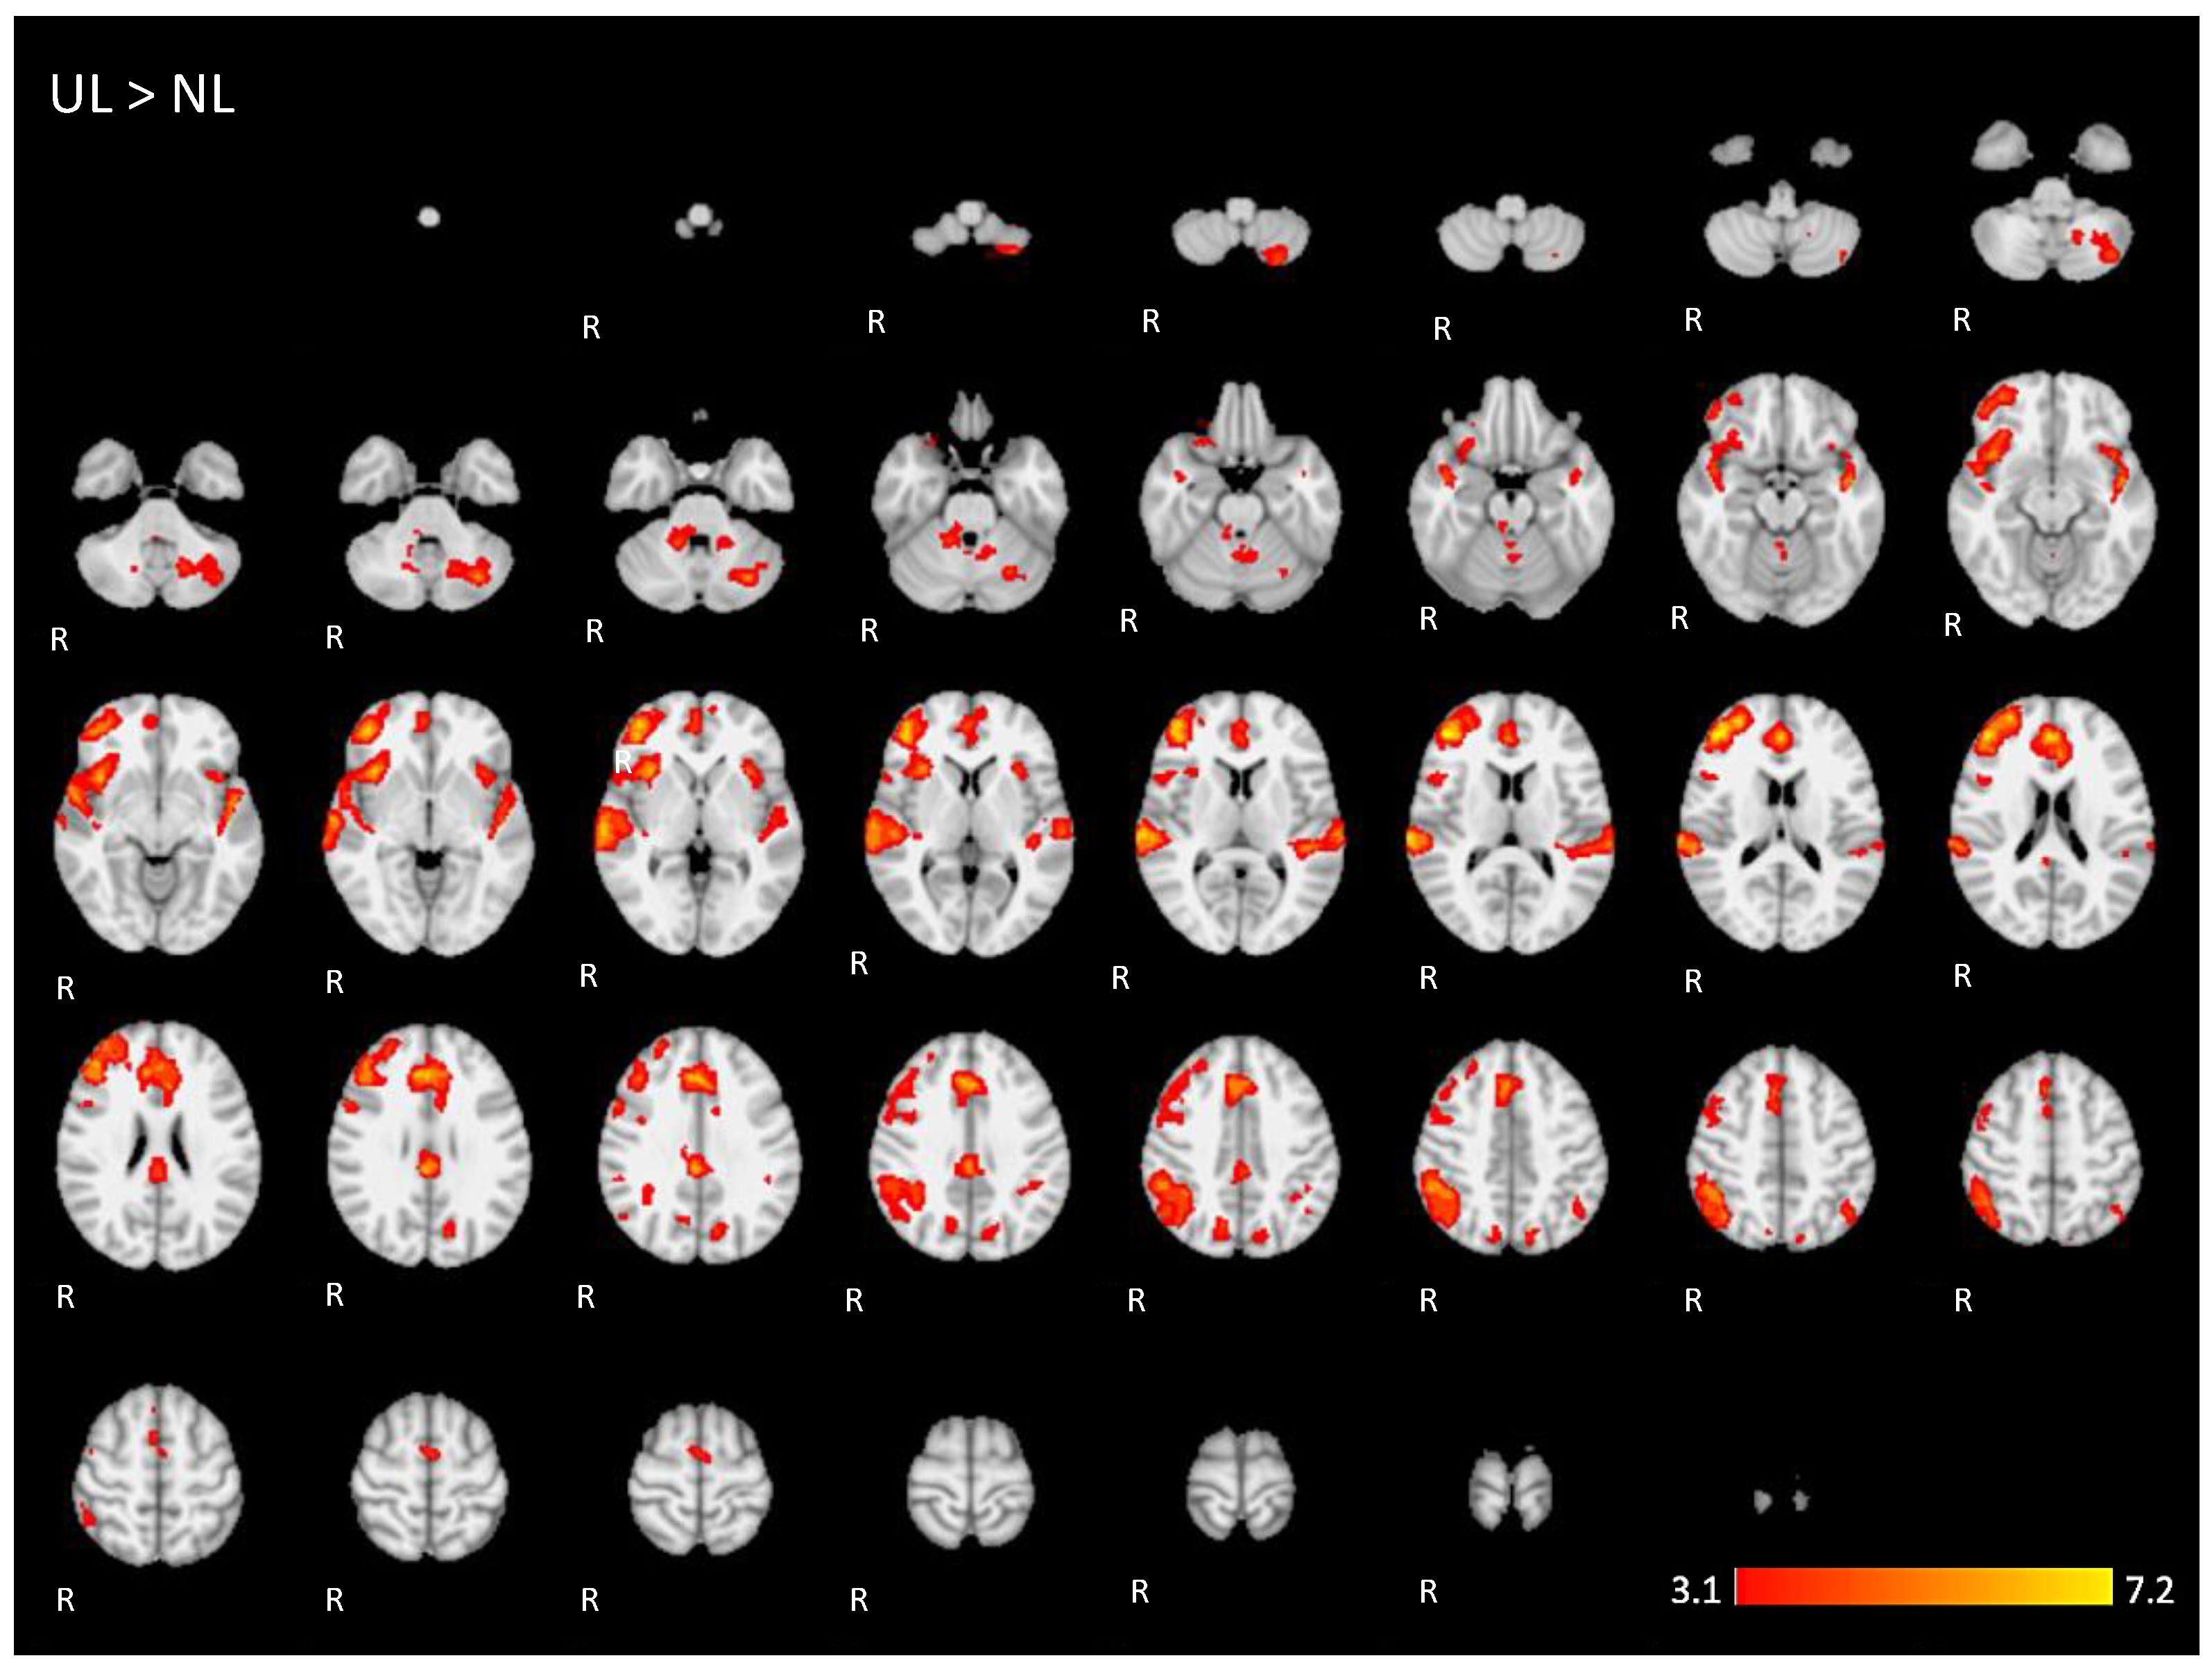

Appendix A. The 2D fMRI Maps of All Brain Slices for Both Active Conditions (NL, UL) and for Both Contrasts (NL > UL and UL > NL)

| UL > NL | 6.1 | 44 | 44 | 14 | Right middle frontal gyrus |

| 5.57 | 2 | 42 | 20 | Right Paracingulate Gyrus | |

| 4.94 | 50 | −42 | 44 | Right supramarginal gyrus, posterior division | |

| 5.01 | −48 | −12 | −6 | Left superior temporal gyrus | |

| 5.08 | −32 | −68 | −34 | Posterior lobe of left cerebellum | |

| 5.18 | 4 | −32 | 30 | Right cingulate gyrus, posterior division | |

| 4.32 | 16 | −46 | −32 | Anterior lobe of right cerebellum | |

| 4.3 | −12 | −74 | 28 | Left cuneus/precuneus cortex | |

| 3.7 | −8 | −54 | −26 | Anterior lobe of left cerebellum | |

| 4.62 | −28 | −70 | −60 | Left cerebellum | |

| 4.11 | −46 | −60 | 48 | Left angular gyrus/inferior parietal lobule | |

| 4.43 | 12 | −68 | 40 | Right precuneus cortex | |